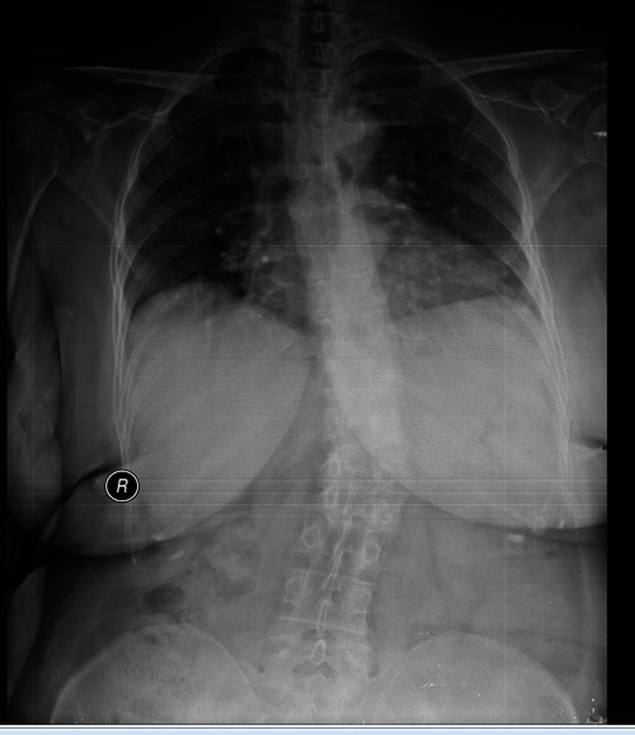

En sık rastlanan postür bozukluklarından biri olan kifoz (kamburluk) ve skolyoz (omurganın sağa ya da sola doğru eğrilmesi) rahatsızlıklarını bir arada yaşayan emekli öğretmen Semra Çağlar, ağrılarından fizyoterapist Elif Akıncı’nın geliştirdiği rubatonik pilates sayesinde kurtuldu. Yaklaşık 10 yıl önce rahatsızlığını fark eden, ablasında ve teyzesinde de aynı hastalık olduğu için bunun kader olduğuna inanarak tedaviyi denemeyen Semra Hanım, Elif Akıncı Pozitif Yaşam Merkezi’ne adım attığı andan itibaren omurga problemlerinin giderilebileceğini anlamış ve bu hastalıkla savaşmaya başlamış. Fizyoterapist Elif Akıncı’nın geliştirdiği egzersiz metodu rubatonik pilates ile ağrıları oldukça hafifleyen, 60 derecelik kifozu 30 dereceye gerileyen ve skolyozunda da ciddi bir düzelme olan Semra Hanım, Elif Akıncı ile tanışmasını, tedavi sürecini ve yaşadığı değişimi şöyle anlatıyor:

Rahatsızlıklarım nedeniyle sırtımda çok ciddi ağrılar vardı. Öyle ki ağrılar yüzünden sırt üstü yatamıyordum. Çok acı çekiyordum. Kifozdan dolayı mide rahatsızlıklarım da başlamıştı. Şubat ayında egzersizlere başladık. Mayıs ayına kadar aralıksız devam ettik. 15. seanstan itibaren bende hızlı bir değişim oldu. 60 derecelik kifozum 30 dereceye kadar geriledi. Doktorum bile çok şaşırdı. Hatta bu sonuç karşısında Elif Hanım ve diğer fizyoterapist arkadaşlar sarıldık, kucaklaştık. Bunun yanı sıra skolyozumda da gerileme olduğunu öğrendim.”